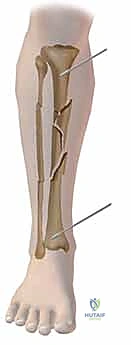

1. عظم الظنبوب (Tibia): وهو العظم الأكبر والأقوى، ويحمل الغالبية العظمى من وزن الجسم.

2. عظم الشظية (Fibula): عظم رفيع يقع على الجانب الخارجي للساق، ويفيد في استقرار الكاحل وتثبيت العضلات.

المشكلة الكبرى في عظم الساق (الظنبوب) تكمن في موقعه التشريحي. الجزء الأمامي والداخلي من هذا العظم يقع مباشرة تحت الجلد (Subcutaneous)، ولا تغطيه طبقة عضلية سميكة تحميه. هذا يعني أنه عند حدوث صدمة قوية (مثل حوادث السير):

* يسهل جداً أن يخترق العظم المكسور الجلد، مما يؤدي إلى كسر مفتوح (Open Fracture).

* تكون التروية الدموية (Blood Supply) في هذه المنطقة أضعف مقارنة بالعظام المحاطة بالعضلات كالفخذ، مما يبطئ من عملية التئام العظام ويزيد من خطر عدم الالتئام (Non-union).